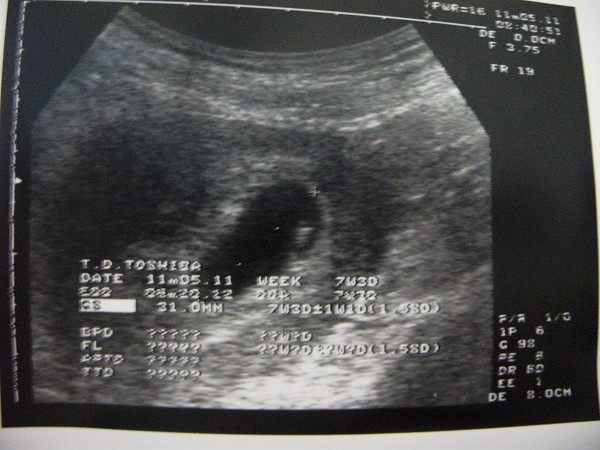

100.11.5 [8W2D]

照到心跳了

也拿到診所發的媽媽手冊

兩週後~準備去醫院開始產檢啦!!!